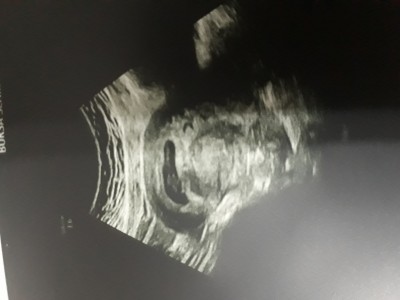

imagekkızlar çok şükür bebeğimi gördüm bisey sormak iistiyorum kesem uzun büyümüş yamuk 10 gün önce yuvarlaktı ve dar gibi degilmi sata göre 9+0 ultrosona göre 7+3üm sizin keseniz nasildi ilk zamanlar

Gebelik haftası 7+3